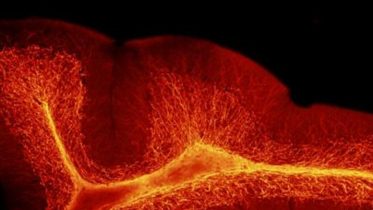

Myelin

Single ALLO injection during pregnancy was enough to avert both the cerebellar abnormalities and the aberrant social behaviors in experimental models. A study in experimental...